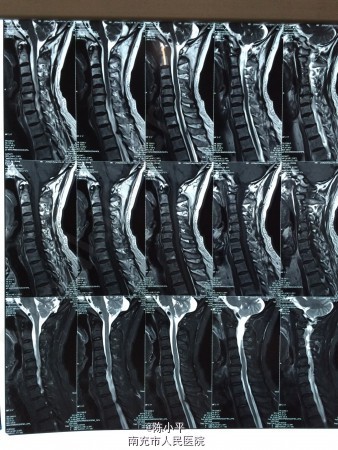

患者男性,56岁,自述肩部无力半年多,会诊后诊断为肌萎缩型颈椎病(颈4.5椎体不稳、颈5/6椎间盘突出),查体:左上肢肌力正常,左拇指麻木,右上肢肱三头肌、右手握力约4级,小指麻木,虎口区肌肉萎缩,双下肢肌力、感觉正常。双手霍夫曼征阴性。